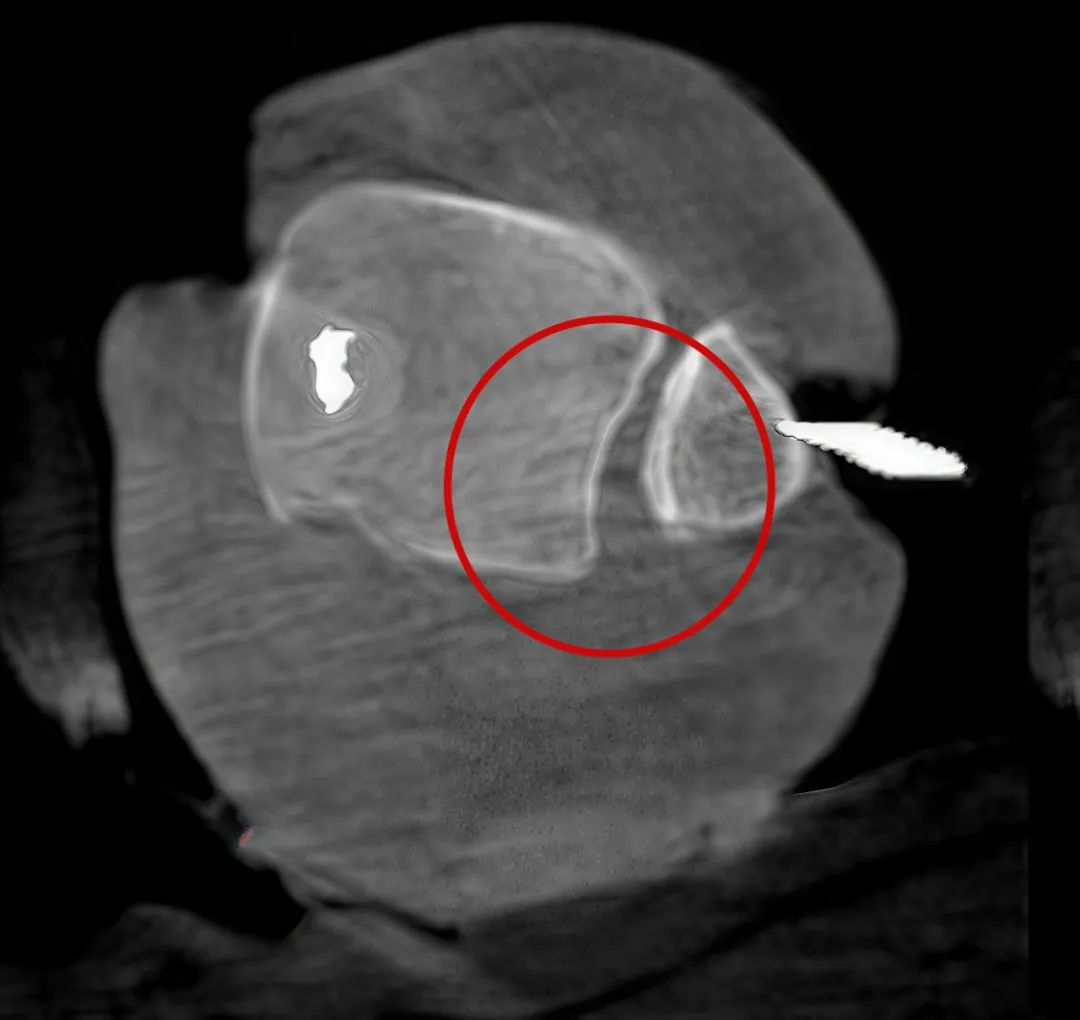

病例3:超聲支氣管鏡下肺活檢(80歲)

三維C形臂還可以創新性地應用在呼吸介入領域。例如,在經皮穿刺或經支氣管鏡肺結節活檢、定位、消融等場景中,用于確認工具是否到達病灶、消融范圍是否完全覆蓋病灶等。

二維影像無法準確判斷工具是否到達病灶

三維各切面影像都顯示工具達到病灶內